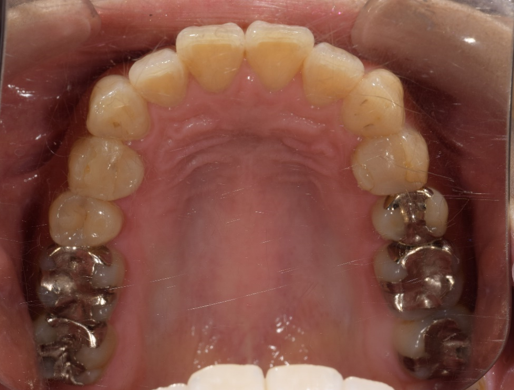

治療前-治療後